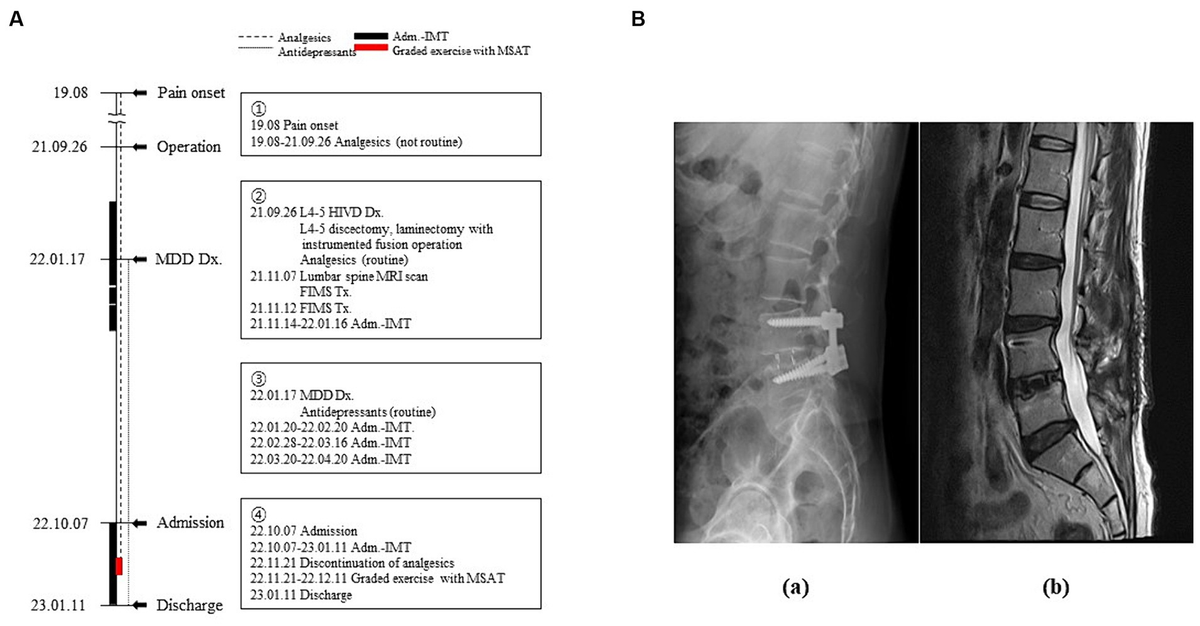

In his medical history, the patient had been diagnosed with L4–5 HIVD and had undergone discectomy and laminectomy with instrumented fusion in September 2021. Before diagnosis and surgery, he received no treatment other than arbitrary analgesic administration when the pain was severe. Although the surgery was successful with no abnormal findings on magnetic resonance imaging (MRI) or computed tomography (CT), the patient had no symptomatic changes in the lower back or lower extremities (Figure 1B). Subsequently, he had to be discharged from the army because of disturbance in his activities of daily living, which had become strikingly worse than before becoming diseased. Moreover, following two ineffective functional intramuscular stimulation (FIMS) treatments, the patient developed helplessness and hopelessness. This triggered depression, manifesting as sleep disturbance, reduced appetite, pessimism regarding his symptoms, and a subsequent attempted suicide. Later that year, he was diagnosed with MDD. Four admissions for integrative medicine treatment, before and after the diagnosis of MDD, did not indicate any pain management strategies (Figure 1A).

Figure 1. Timeline of the patient’s medical history. (A) Timeline of the medical events between the onset of the pain and the current treatment period. Narrative demonstrations of the timeline are in the boxes. (B) Radiological images of the lumbar spine (a: lateral view of X-ray image, b: Sagittal section of T2-weighted magnetic resonance image). Adm, admission; Dx, diagnosis; FIMS, functional intramuscular stimulation; HIVD, herniated intervertebral disc; IMT, integrative medicine treatment; MDD, major depressive disorder; MRI, magnetic resonance imaging; MSAT, motions style acupuncture therapy; Tx, treatment.